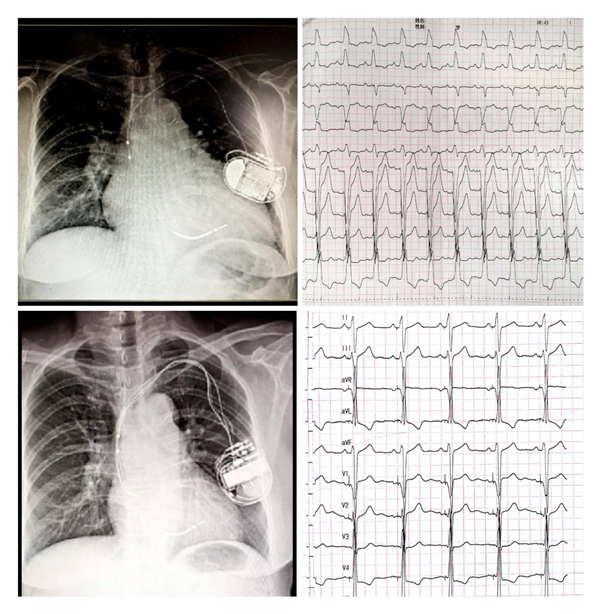

爱情岛论坛 为国内较早开展左束支起搏(LBBP)的中心之一,自2018年1月开展福建省首例LBBP以来,至今累计例数已近200例。中心采用黄伟剑教授的标准术式,手术成功率高、并发症少,随访导线参数稳定。此前起搏团队为1例外院CRT失败转诊爱情岛论坛 的患者实行左束支起搏治疗得到了良好的疗效,LVD从80mm 缩小至52mm,LVEF 从24%升高至60%,心脏完全恢复正常。目前厦心常规开展这一技术以造服更多的心衰患者。

(上图左上为CRTD术前,外院植入ICD2年,右上是自身完左心电图;左下为CRTD术后一年,右下为CRTD术后心电图)